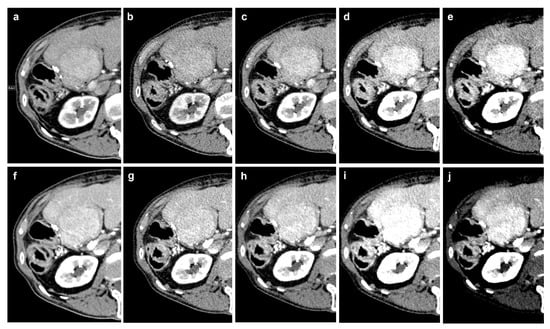

PCD-CT was performed at 120 kVp in QuantumPlus mode (obtaining full spectral information) and polychromatic T3D images were generated. Slice thickness was 3 mm for both series; single slice collimation was 0.4 mm. The kernel was set at Br40f for both phases with quantum iterative reconstruction factor 2 (QIR 2). The spiral pitch factor was 0.8. Virtual monoenergetic images (VMI) were reconstructed at 40 to 70 keV for the PCD-CT (Figure 1).

Figure 1. Example of the different reconstructions in an HCC lesion: (ae): arterial phase imaging (T3D, 70 keV, 60 keV, 50 keV, 40 keV); (fj) portal venous imaging (T3D, 70 keV, 60 keV, 50 keV, 40 keV).